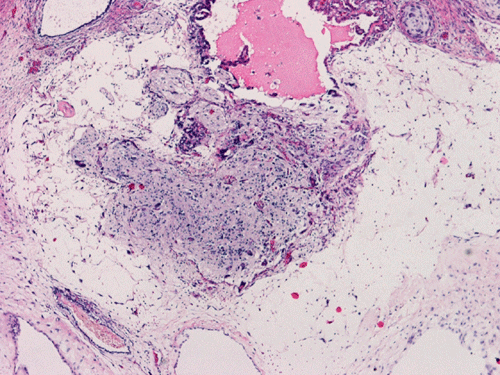

The patient was a 5 year-old Vietnamese boy who presented with the chief complaints of headaches, vomiting, and ataxia.  CT scan revealed a pineal tumor with small calcifications and hydrocephalus (Panel 1).  On MRI, the mass is a well demarcated midline mass involving the pineal area. There is also heterogeneous enhancement and cystic component (Panel 2 and 3).

The excised specimen consists of multiple fragments of tan, soft tissue, 5.0 x 2.0 x 1.0 cm in aggregate, for examination. On gross examination, neither calcified tissue nor hair were found. An intraoperative frozen section and cytologic preparation was performed which revealed mature intestinal element, skin and small amount of hair. No germinoma element, yolk sac tumor (endodermal sinus tumor) element, embryonal cell carcinoma, or immature teratoma component was present in multiple specimens submitted for frozen section. Although a minute amount of hair was revealed on the frozen section, gross examination of the submitted tissue does not identify any hair or calcified tissue. An intraoperative diagnosis of teratoma with only mature element present was made.

The entire specimen was submitted for histologic examination. The bulk (over 99%) of the tumor was composed predominantly of mature intestinal elements (Panel A, B, and C) and skin, respiratory type mucosa, cartilage, and small amount of mature neural parenchymal tissue of the central nervous system (Panel D and E). Neither immature nor malignant elements are present. Small microscopic foci of well demarcated, neural parenchymal tissue with increased atypia (arrow in panel F) are noted. On higher magnification (Panel G and H), these areas contain large, bizarre appearing cells with dark chromatin but no prominent nucleoli. There are also scant multinucleated cells and mineralized substances (arrow in Panel H). Another example of these foci is illustrated in Panel I, J, and K. These atypical foci comprised less than 1% of the volume of the tumor. They are all microscopic in size and show no evidence of expansion or invasion into the surrounding tissue.